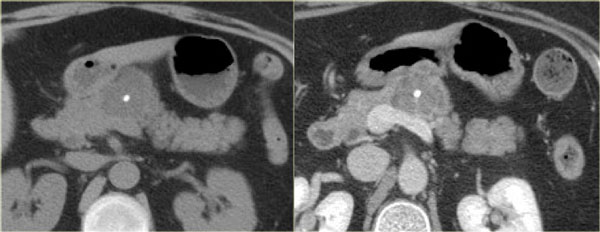

Another example of a serous cystic neoplasm (Fig).

The contrast-enhanced image on the right shows a hypodense lesion with central calcification in the body of the pancreas and subtle enhancement of septations

Notice that on CT it is very difficult to appreciate the cystic nature of these lesions and you might think that you are dealing with a pancreatic adenocarcinoma.

MRI will easily demonstrate the cystic nature of these lesions (fig).